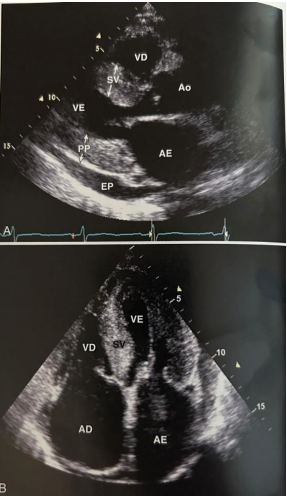

Ecocardiograma transtorácico com as seguintes imagens:

Braunwald – Tratado de Doenças Cardiovasculares – 9ª Ed. Cap. 15. Figura 15-78.